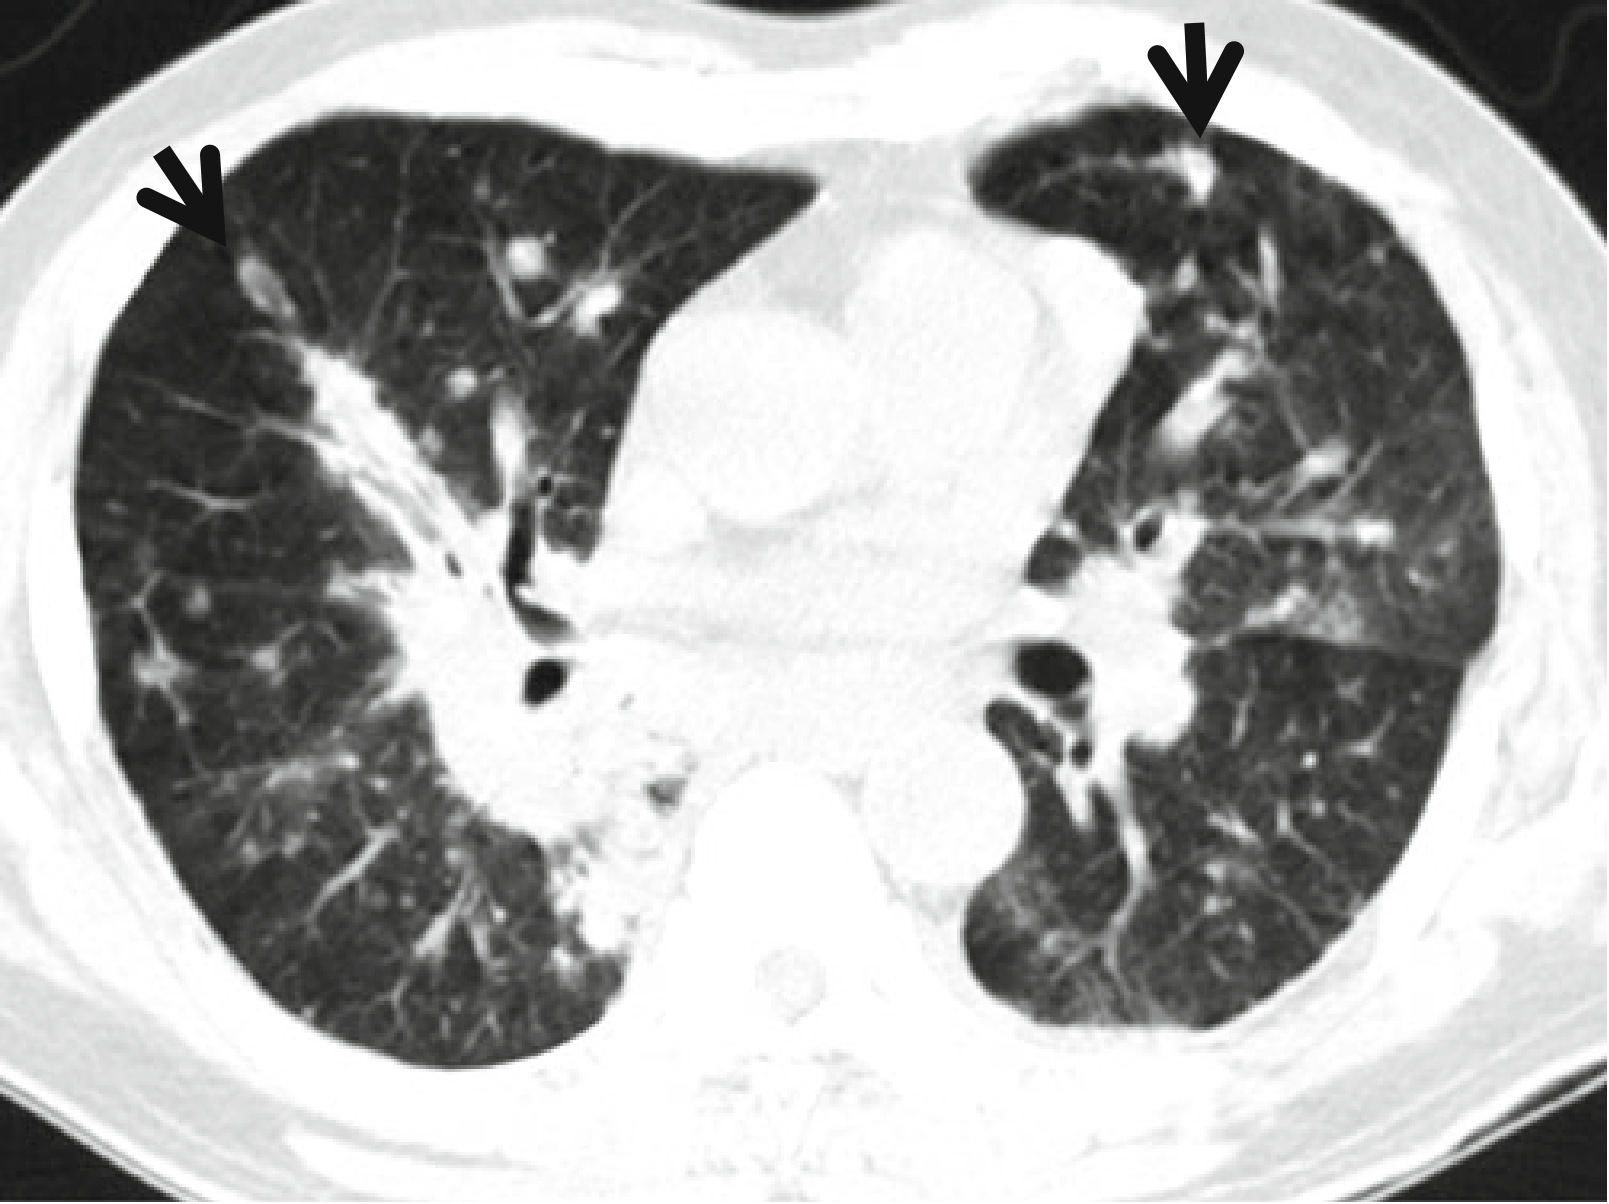

b398ddc9cd001c8cd22d25e668867f22.png9fe20fb2010a729413f7c5ddcc088e4c.png图 8.3 肺毛霉菌病。

女,17岁,5年前患有间变性大细胞淋巴瘤。

(a,b)CT增强扫描(层厚=5.0mm)连续肺窗于右侧中间段支气管水平可见致密实变影,周围绕以GGO(晕征的一种)。请注意看内部的反晕征(箭头所示),由中央的坏死区及周围环状强化的实变区组成。

(c)在可视化胸腔镜下行左肺上叶楔形完全切除术,大体标本切面可见侵袭性真菌的实变区及坏死病灶(箭头所示)。

(d)高倍光镜(×100)下可见坏死性肺炎。请留意伴有宽大的菌丝(箭头所示)、薄壁及无(或极少)分隔的真菌。